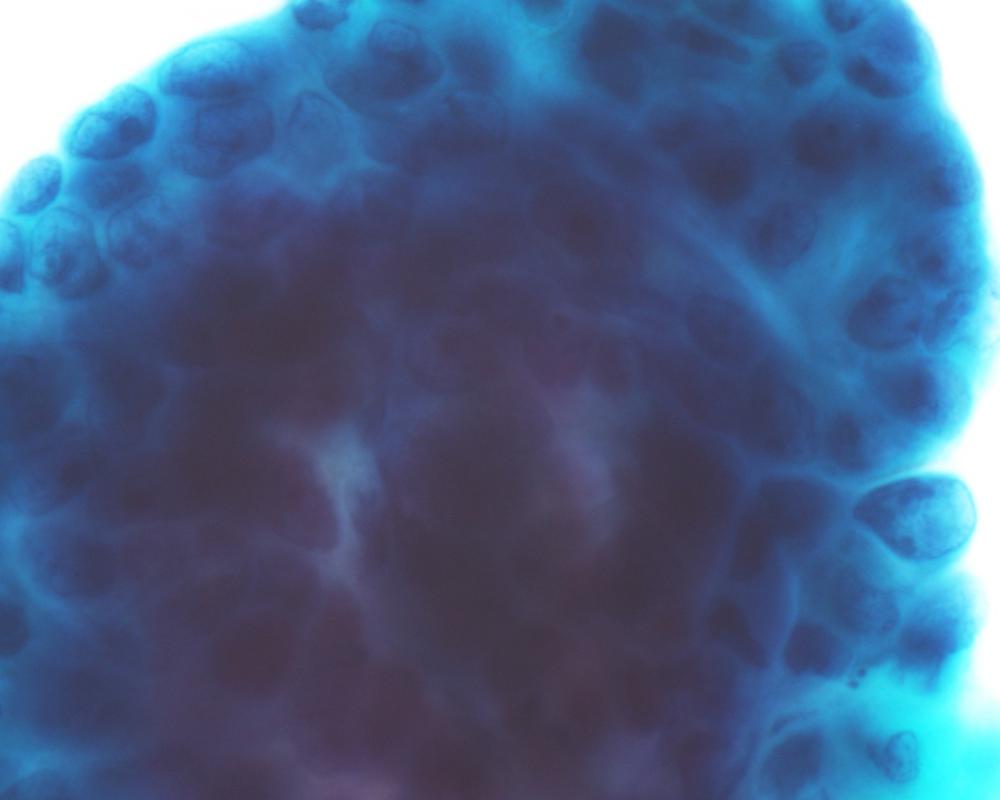

第35回日本臨床細胞学会九州連合会学会(宮崎)スライドカンファレンス症例3

種別:呼吸器

出題:福岡大学病院 病理部・病理診断科 濵﨑 慎 先生

| 年齢 | 80歳代 | 性別 | 男性 |

| 採取部位 | 左肺下葉 | 採取方法 | 腫瘍捺印細胞診 |

臨床所見

既 往 歴:労作性狭心症(バイパス術後)、高血圧症、高脂血症

生 活 歴:喫煙40本/日×49年

現 病 歴:労作性狭心症(バイパス術後)のフォロー中に貧血を指摘、精査中に左肺下葉に腫瘤を認め、確定診断目的で切除の方針となった。

| 正解 | 2.腺癌 |

▼選択肢及び投票結果

| 1.扁平上皮癌 | 8件 | (8.2%) | |

| 2.腺癌 | 39件 | (40.2%) | |

| 3.大細胞神経内分泌癌 | 27件 | (27.8%) | |

| 4.悪性胸膜中皮腫 | 6件 | (6.2%) | |

| 5.悪性黒色腫 | 17件 | (17.5%) | |

| 投票総数 | 97件 | (100%) |